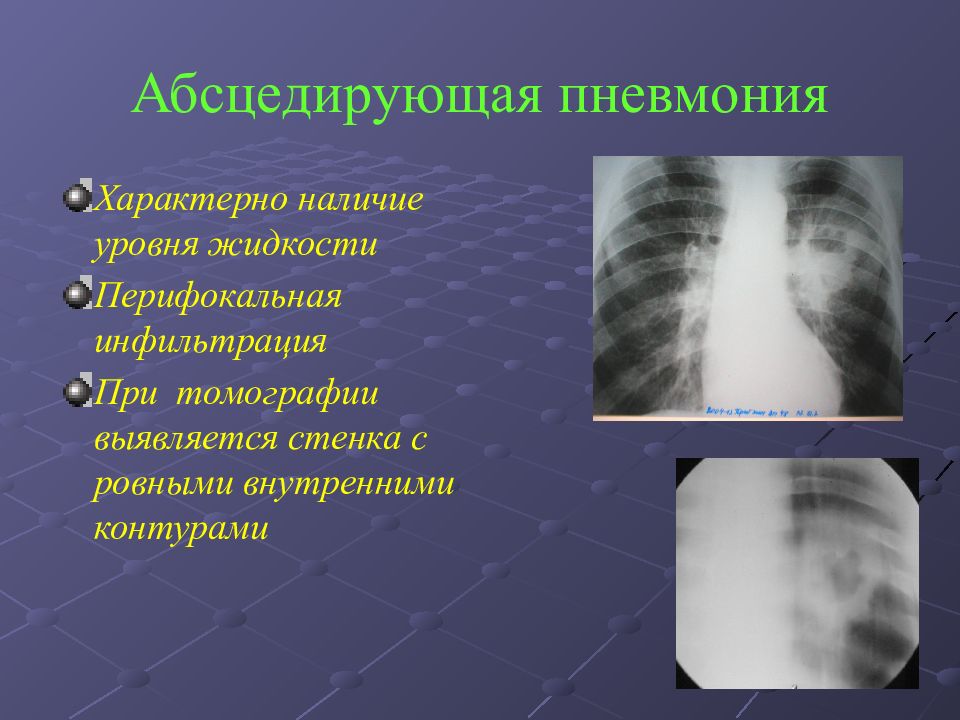

Медицинская тема: легочные осложнения при пневмонии